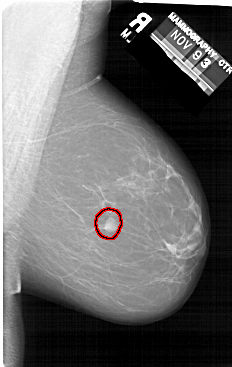

A_1412_1.RIGHT_MLO

RIGHT_MLO LINES 6601 PIXELS_PER_LINE 4171 BITS_PER_PIXEL 12 RESOLUTION 43.5 OVERLAY

FILE: A_1412_1.RIGHT_MLO.OVERLAY

TOTAL_ABNORMALITIES 1

ABNORMALITY 1

LESION_TYPE MASS SHAPE IRREGULAR MARGINS CIRCUMSCRIBED

ASSESSMENT 4

SUBTLETY 5

PATHOLOGY BENIGN

TOTAL_OUTLINES 1

BOUNDARY